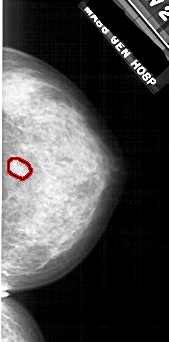

FILE: A_1808_1.RIGHT_MLO.OVERLAY

TOTAL_ABNORMALITIES 1

ABNORMALITY 1

LESION_TYPE MASS SHAPE IRREGULAR MARGINS ILL_DEFINED

ASSESSMENT 4

SUBTLETY 2

PATHOLOGY BENIGN

TOTAL_OUTLINES 1

BOUNDARY